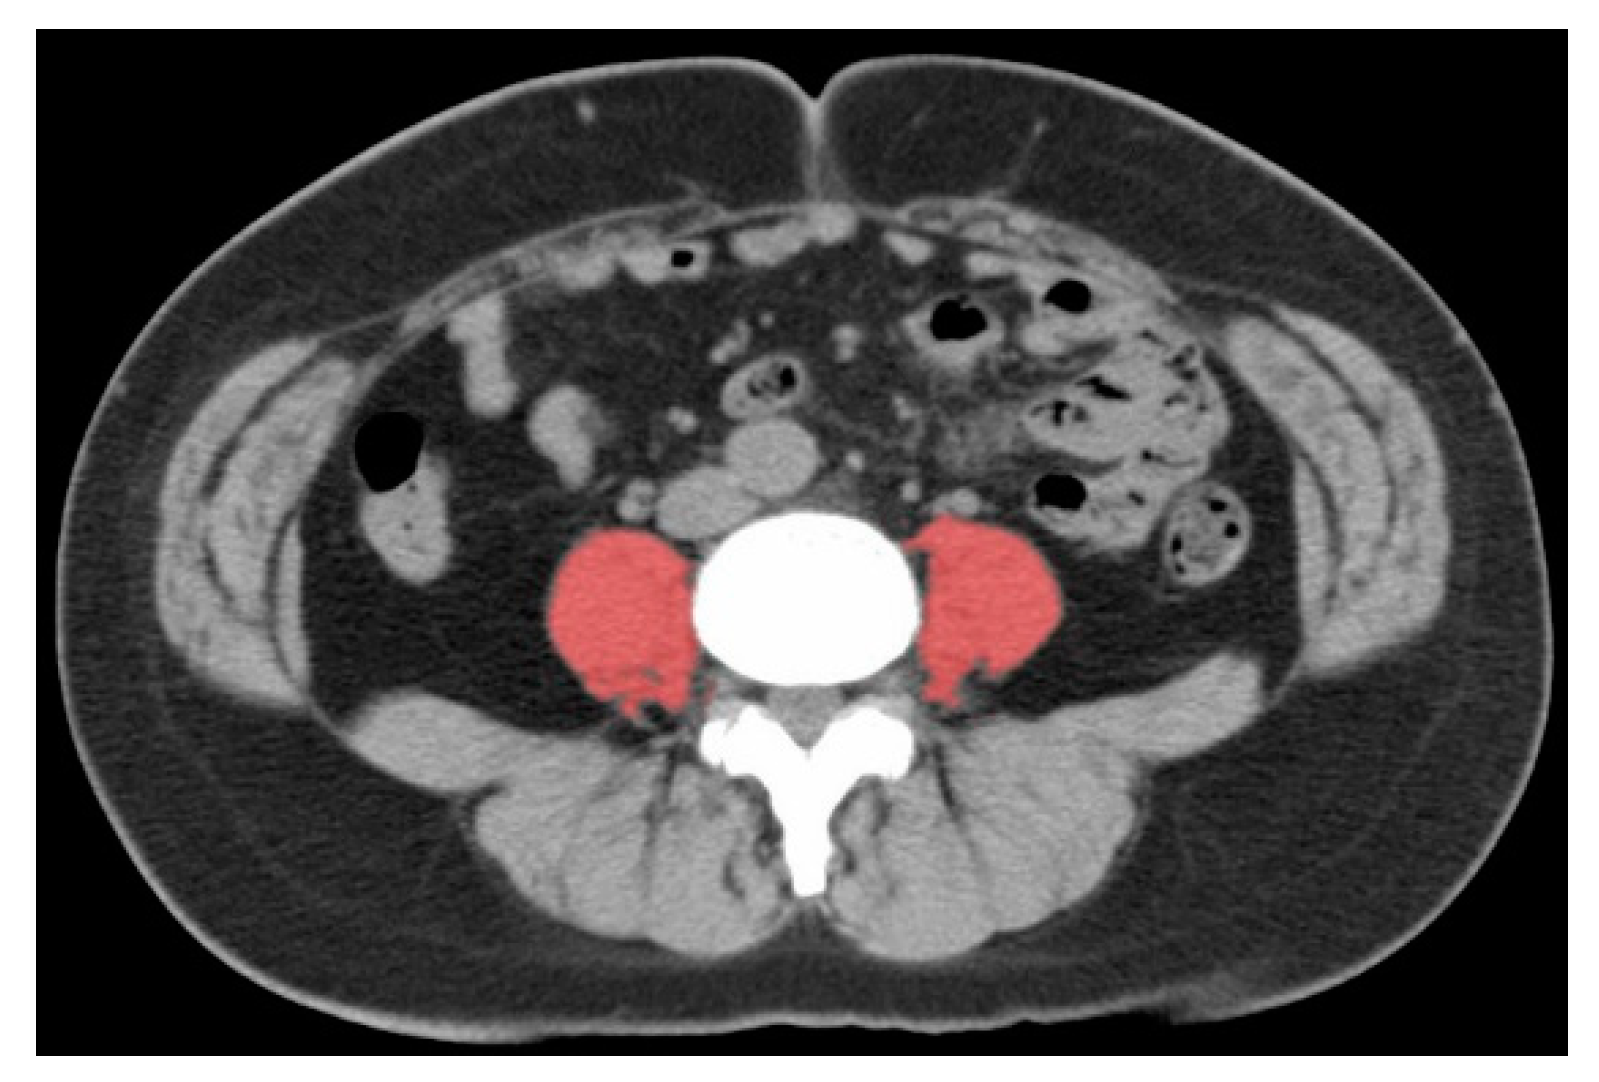

The calculation of PMI was available in 369 (97%) patients. Figure 2 shows the measurement of the psoas muscle used for PMI calculation.

Figure 2.

Image of the total bilateral psoas muscle area at the L3 level. The red area is measured as the psoas region.

The cross-sectional area of the psoas muscle at the caudal end of the L3 level was measured by E.I. and M.N. using SYNAPSE VINCENT software (Fujifilm Medical, Tokyo, Japan) at diagnosis and 2 years after the patients started taking the supplements. L3 psoas muscle cross-sectional area was identified and quantified using Hounsfield unit thresholds (−29 to +150) [21]. The total bilateral psoas area at the L3 level was normalized for height using the following equation:

The psoas muscle index (PMI) cut-off values for sarcopenia in the present analysis were 6.36 (cm2/m2) for males and 3.92 (cm2/m2) for females based on a previous report defining sarcopenia in Asian adults [22]. The definition of sarcopenia was based only on skeletal muscle mass, not muscle weakness and not reduced physical activity, in the present analysis.